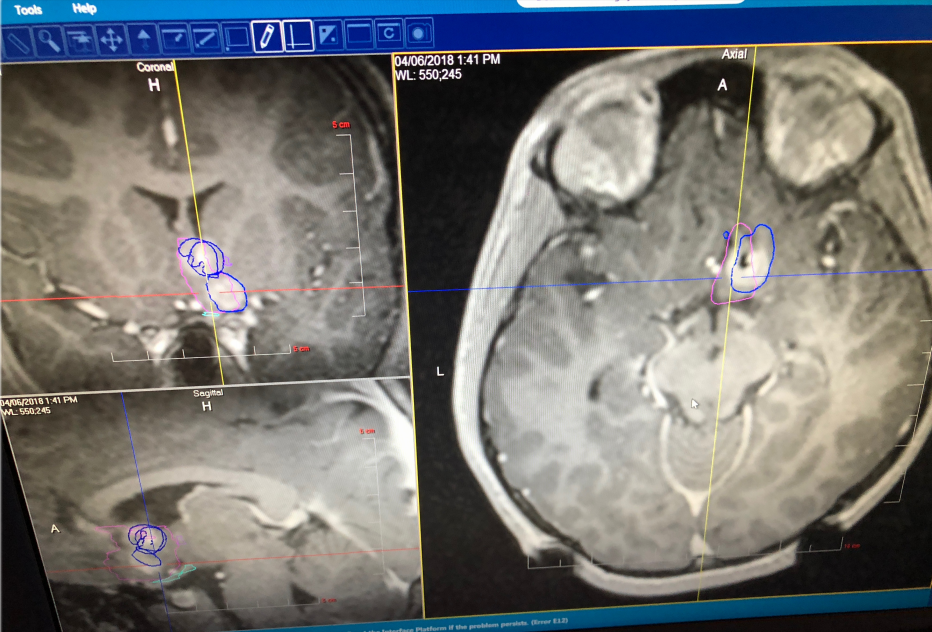

Rutka教授案例分享:局灶性皮质发育不良,复发癫痫

一名患有额叶癫痫的12岁男孩,伴有运动机能亢进的癫痫发作,神经成像检查结果显示:右侧额内侧下基底病变,他接受了开颅右额叶病灶切除术,病理资料显示为局灶性皮质发育不良(FCD),术后三个月无癫痫发作。

不幸的是,三个月后他的癫痫复发了,但Rutka教授不希望孩子在短时间内再次接受开颅手术,因此与患者家属深入沟通后决定为其进行激光间质热疗(LITT)。

Rutka教授和他的团队正在为其手术

术后男孩便没有癫痫发作了,而且近期随访显示其生长发育和智力发育正常,且癫痫并未复发。